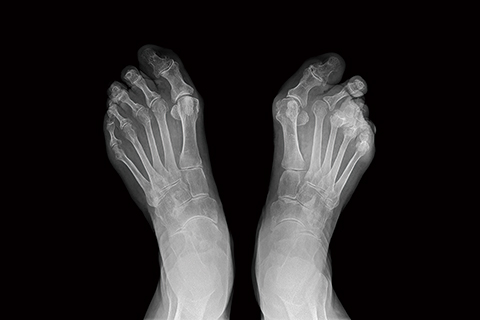

• 류마티스관절염

자가 면역 체계 이상으로 발생하는 염증성 관절질환을 말합니다.

류마티스관절염 치료방법

• 비수술적 치료 약물치료, 물리치료, 재활운동치료

• 수술적 치료 무릎 관절경 수술